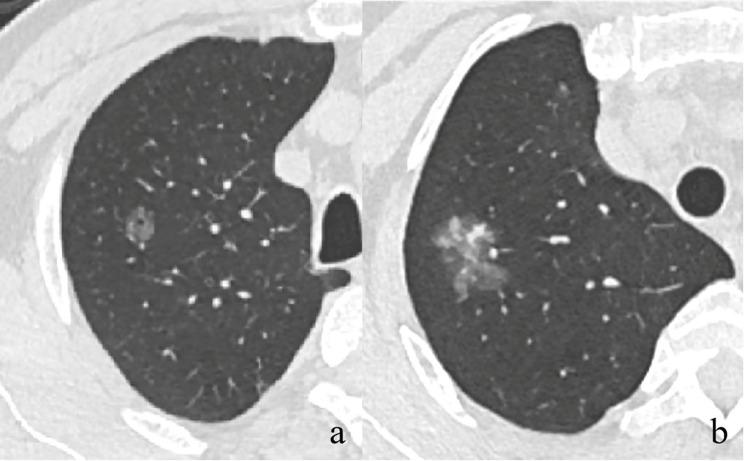

Neoplastic ground glass nodules (GGNs) are relatively indolent tumors, with slow progression in invasiveness and computed tomography (CT) features. This study aimed to explore the correlation between pathological and CT characteristics and gene mutations in neoplastic GGNs.

METHODS

We retrospectively analyzed 1,348 neoplastic GGNs from January 2019 to November 2022, including 290 adenocarcinomas in situ (AIS), 448 microinvasive adenocarcinomas (MIA), and 610 invasive adenocarcinomas (IAC). The correlations between patients' characteristics, pathological subtypes and grades, CT features, changes in follow-up, and gene mutations were analyzed.

Solid component (odds ratio [OR] = 1.493; P = 0.014), larger size (OR = 1.049; P = 0.006), ill-defined boundary (OR = 1.368; P = 0.027), and lobulation sign (OR = 1.824; P = 0.001) were revealed as independent CT predictors of gene mutation. From AIS to IAC, the epidermal growth factor receptor (EGFR) mutation rate significantly increased (P < 0.01), while the kirsten rat sarcoma viral oncogene (KRAS) and the anaplastic lymphoma kinase (ALK) mutation rates significantly decreased (P < 0.05). Among IACs, mutation rate was the highest in the intermediate-grade ones (P < 0.05). Gene mutations were more frequently detected in nodules showing changes during follow-up (76.3% vs. 61.1%, P = 0.02), especially in those with more than 2-year follow-up (77.1% vs. 43.7%, P = 0.023). However, the specific changes were not associated with gene mutations (P = 0.273).

CONCLUSIONS

Gene mutations in neoplastic GGNs were associated with CT features, pathological subtypes and grades, and changes observed during long-term follow-up.